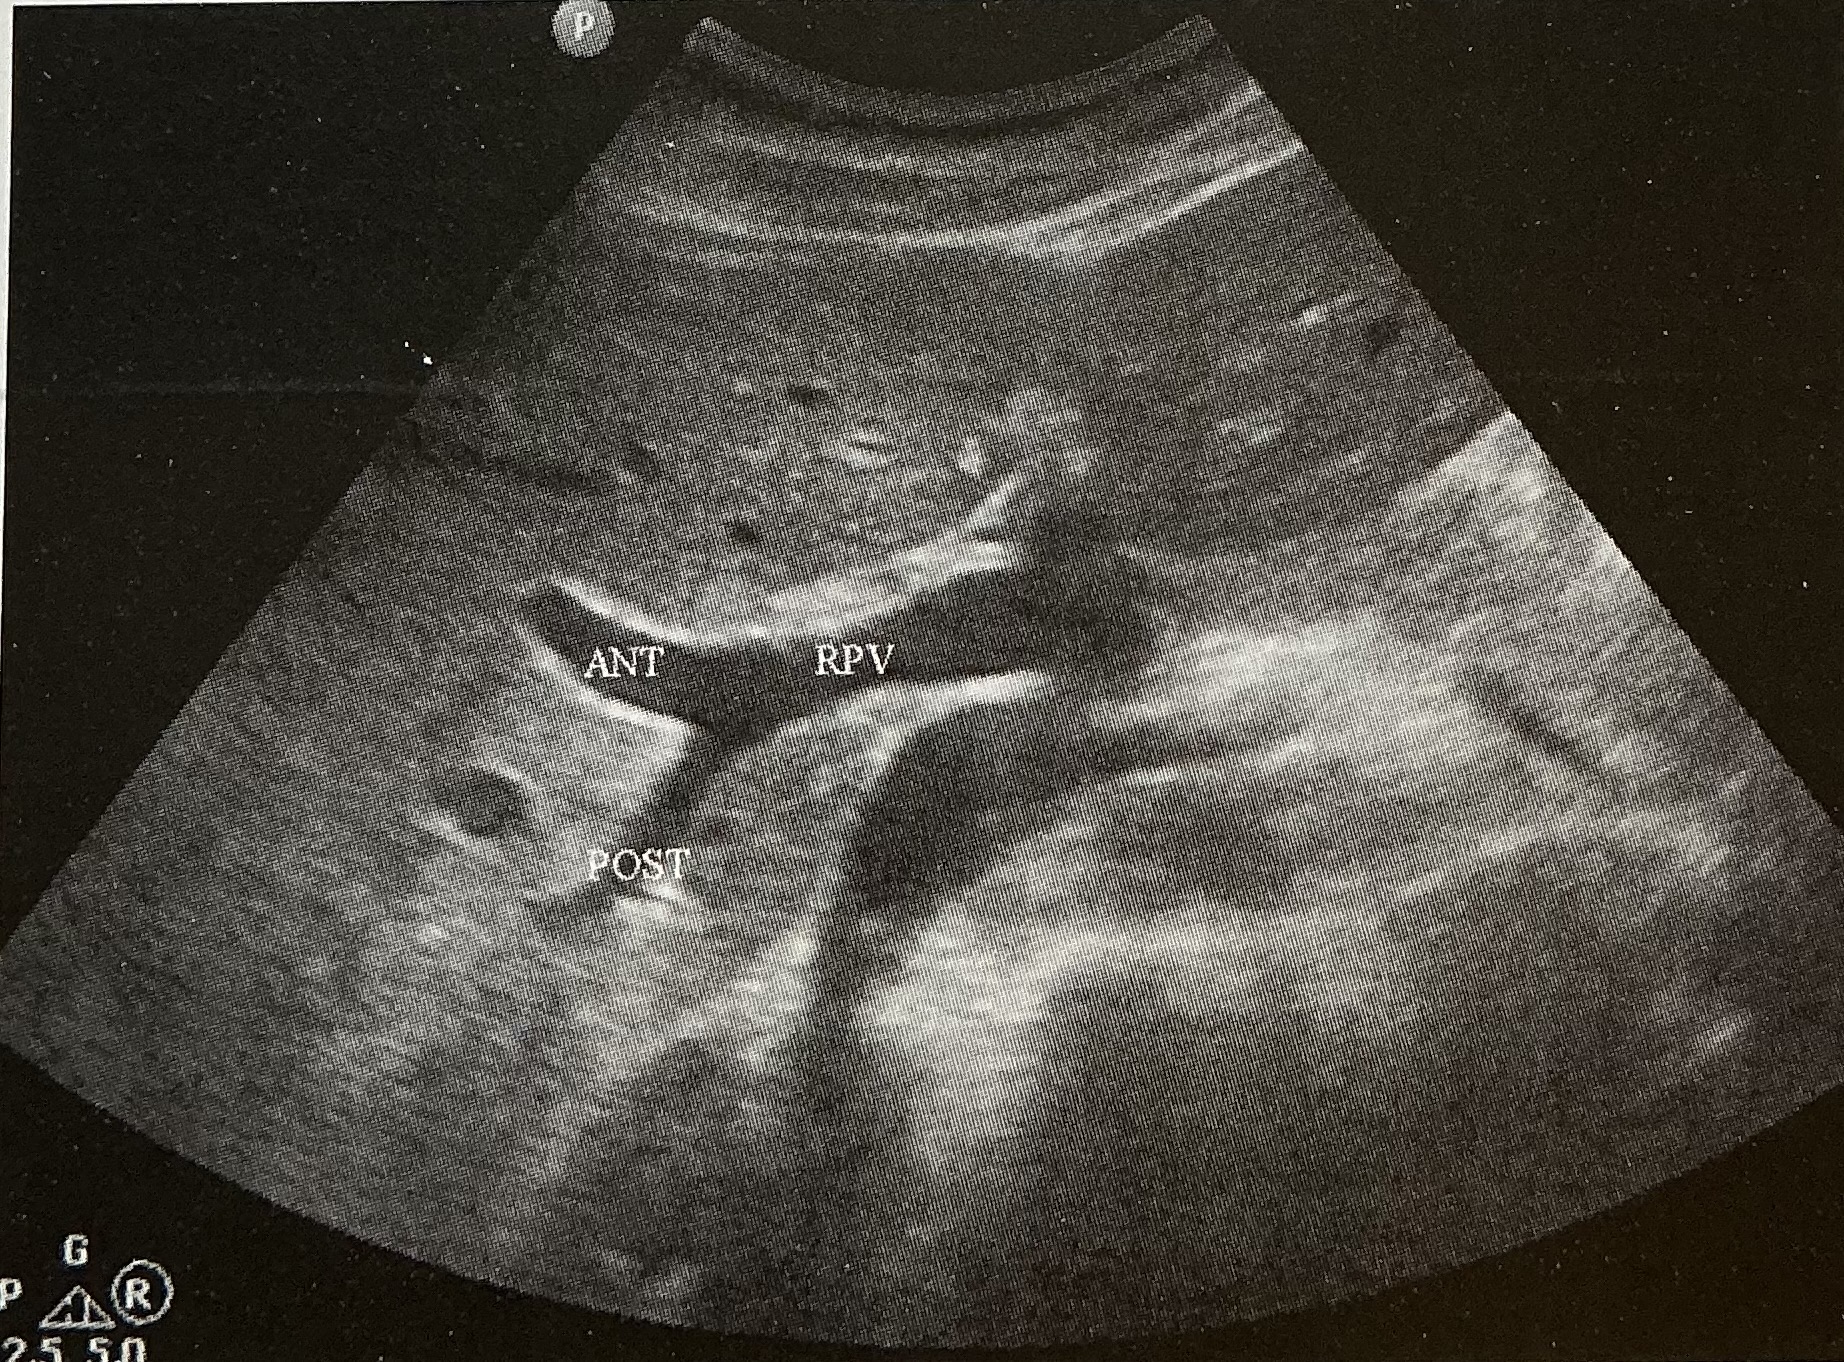

What is the sonographic criteria for differentiating the portal veins and hepatic veins?

origin and drainage; echogenic walls; branching patterns; caliber changes and Doppler signal; segmental locations

Label this picture

what sign is it depicting

Why does this happen?

What sign does the hepatic veins normally depict?

Canadian moose sign

Dilatation from right heart failure

Playboy bunny sign